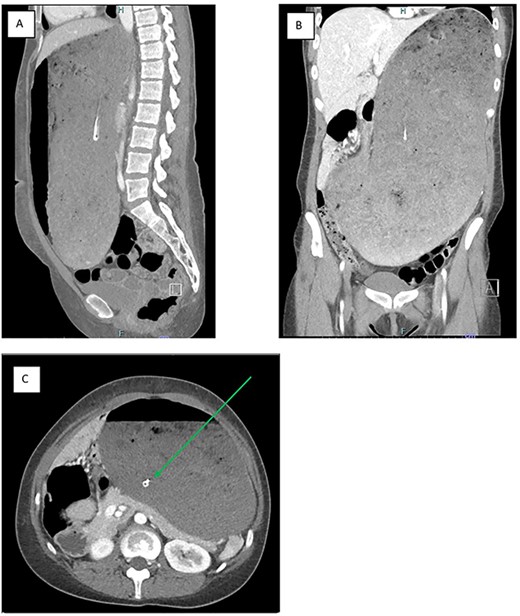

The patient presented with acute abdominal pain and distension with an inability to vomit after a large binge, consisting of litres of rice, noodles, vegetables, meat, drinks and dessert, at a ‘hotpot’ restaurant. She appeared distressed and was unable to lie flat, with examination revealing gross abdominal distention. She had an unremarkable routine laboratory workup, including a normal white cell count and lactate level. She received fluid resuscitation. An 18 French nasogastric tube was inserted successfully into the stomach, but no gastric content was able to be aspirated. A computed tomography (CT) of the abdomen and pelvis demonstrated a well-positioned nasogastric tube within a grossly distended stomach that passed inferiorly below the level of the pelvic brim, occupying most of the abdominal cavity (Fig. 1). The pylorus and duodenum were collapsed, demonstrating no passage of food distally. There was no imaging evidence of perforation.

a CT image of the gross gastric distension extending into the pelvis secondary to a binge episode in the (A) sagittal, (B) coronal and (C) axial slices; the nasogastric tube (green arrow) is appropriately placed within the gastric lumen